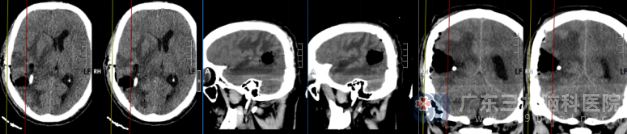

术后头颅CT检查提示:右侧颞枕叶-脑室后角占位切除术+脑室外引流术后改变,建议随诊复查。